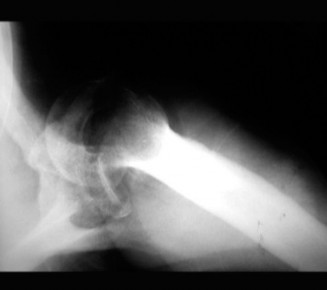

The initial radiographs from the outside facility, when acquired and reviewed, were indeed subtle but retrospectively demonstrated a clear anterior glenohumeral dislocation that had been unfortunately missed. The primary error in the initial evaluation was the reliance on a single, non-orthogonal anteroposterior view without a dedicated axillary or lateral scapular projection. On the current presentation, a complete trauma series of the shoulder was obtained, consisting of a true AP glenoid (Grashey) view, an axillary lateral view, and a scapular Y-view.

The AP Glenoid View showed the humeral head displaced anteriorly and medially relative to the glenoid fossa, lying inferior to the coracoid process. Crucially, the normal elliptical overlap of the humeral head and the glenoid (the "half-moon" sign) was absent. Instead, the humeral head was completely medial to the anterior glenoid rim.

The Scapular Y-View provided additional confirmation, demonstrating the humeral head lying anterior to the intersection of the coracoid, acromion, and scapular body (the center of the "Y"), further corroborating the subcoracoid position of the dislocation.